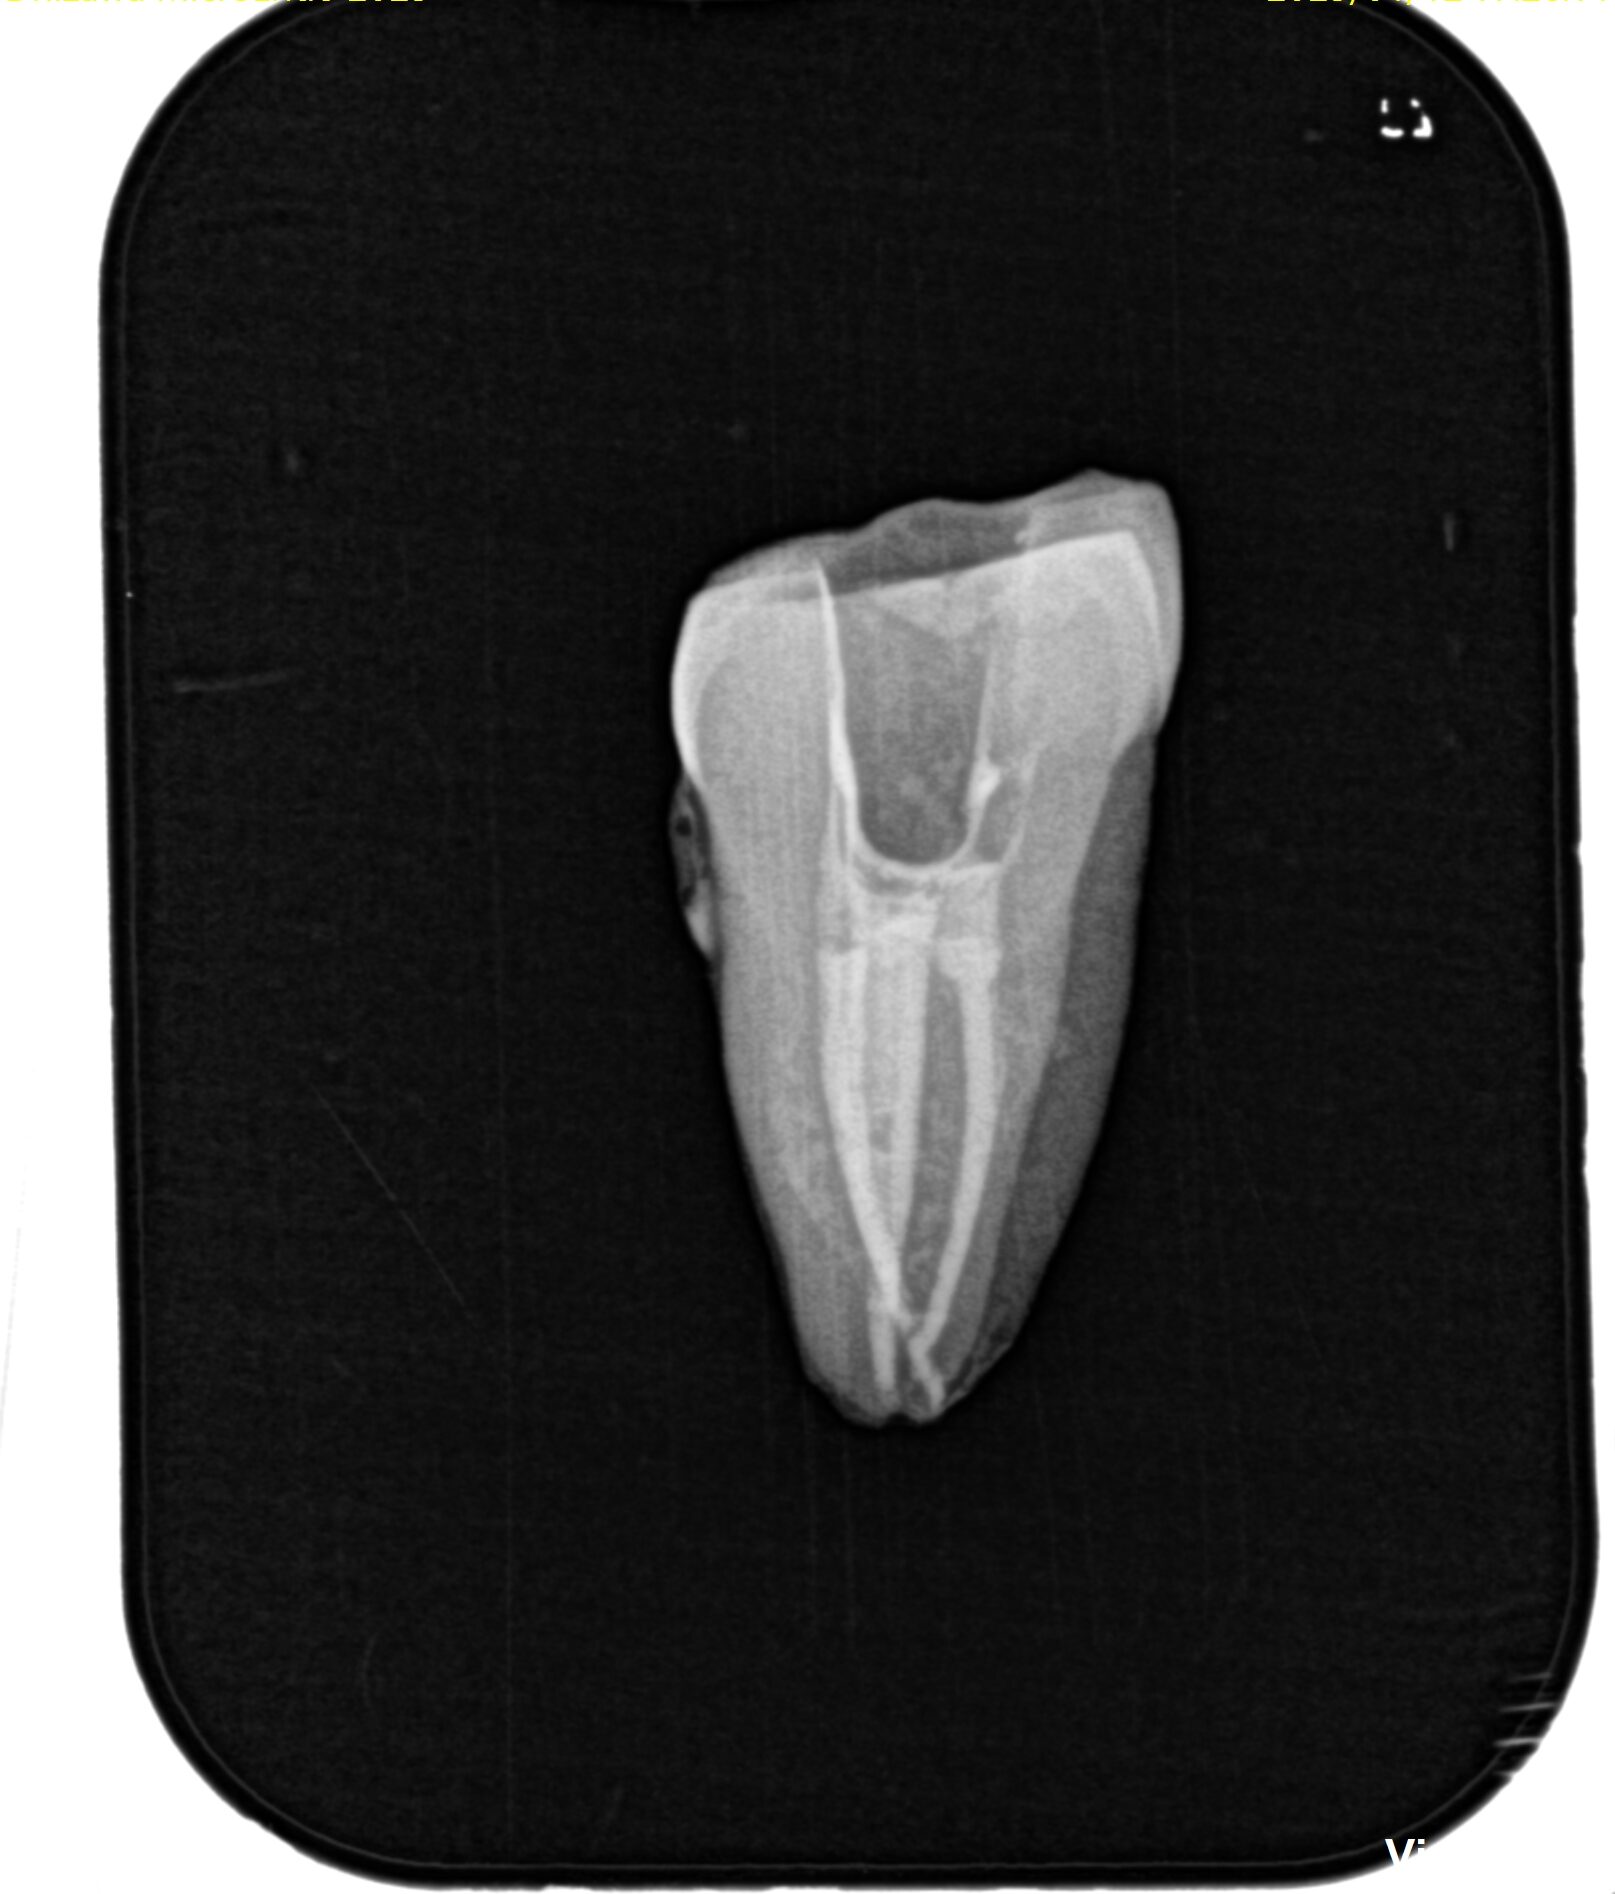

翌日曜日は実習を行なった。

合流も再現ができていた。

毎日練習すれば誰でもうまくなります。